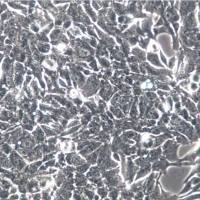

细胞名称:Mino 人套细胞淋巴瘤细胞

组织来源:B淋巴细胞

培养条件:RPMI-1640 +10% FBS

形 态:悬浮;淋巴母细胞样